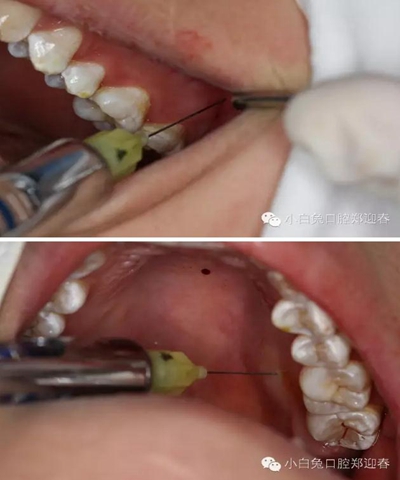

2%利多卡因4ml行下牙槽神經(jīng)阻滯麻醉,必蘭0.3ml行頰粘膜局部浸潤(rùn)麻醉。

同期準(zhǔn)備拔除28,28頰側(cè)牙尖萌出,余牙面均被牙齦覆蓋。

首先,必蘭0.5ml行上牙槽神經(jīng)和腭前神經(jīng)阻滯麻醉。

采用創(chuàng)面不縫合的切瓣方式

充分暴露牙冠部分